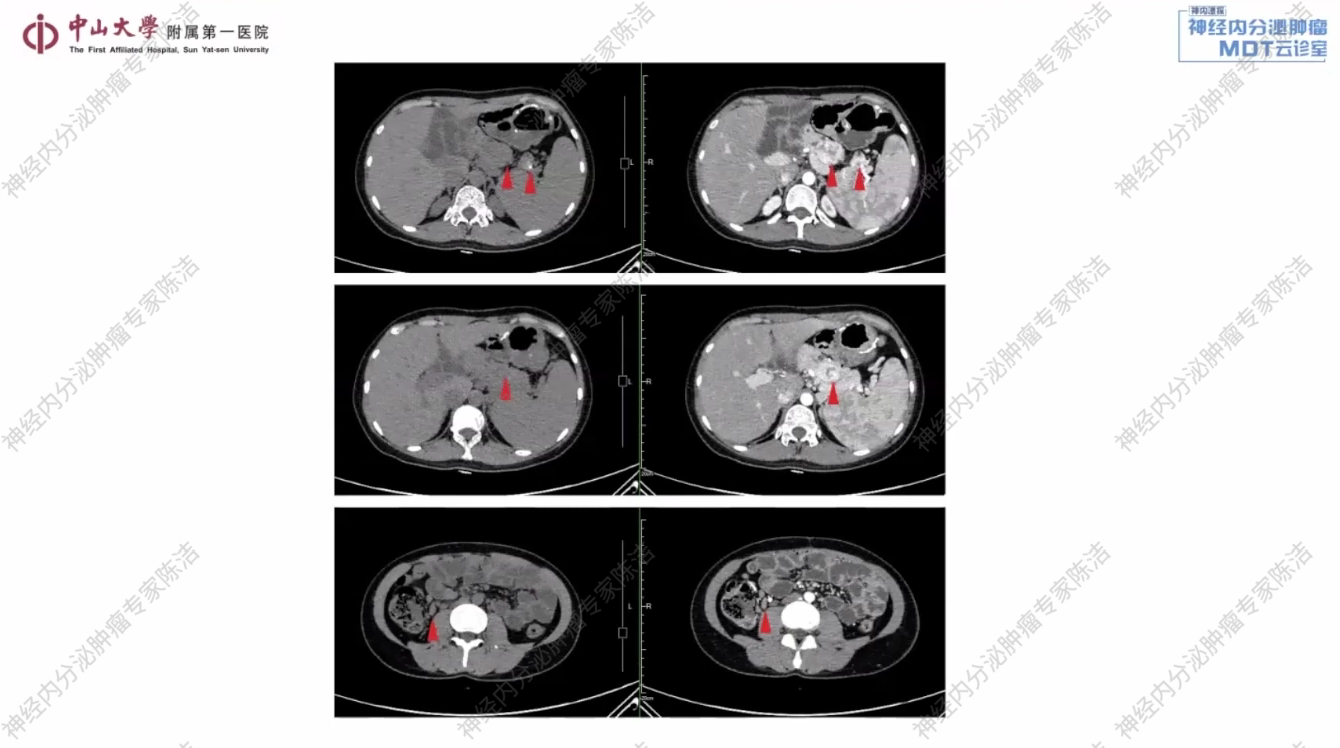

CT:胰腺多发肿物,侵犯脾静脉,考虑肿瘤复发;胰周、脾周、胃周、前腹腔及中腹腔静脉曲张;胰腺多发小囊肿,右侧髂血管旁、肠系膜区、右结肠旁多发结节,考虑转移瘤。

核医学科徐俊彦教授:该患者胰腺体部和尾部各可见一个软组织结节。其中,胰体部结节较为明显,中央密度不均,并伴有部分囊性坏死区;胰尾部结节则周围伴有钙化。PET/CT显示,这些结节均高度表达生长抑素受体,且FDG代谢呈轻度活跃。综合分析,该患者的肿瘤倾向于分化良好,分级不超过G2级别的神经内分泌肿瘤。对于这类SSTR表达阳性的神经内分泌肿瘤,68Ga-PET/CT在明确诊断和分期上具有重要价值。同时,FDG-PET/CT显示肿瘤具有中度糖代谢活性,这与G2的分级相符。双核素显像为疾病的全面评估和诊断提供了关键信息。

放射诊断科汤伟教授:该患者胰腺体尾部及脾门区可见多个富血供占位。此外,在右侧结肠旁沟及腹膜后区域,红箭头所标示的小结节考虑为转移性淋巴结。综合判断,此为多发性胰腺NET伴腹膜后及结肠旁沟淋巴结转移。舒尼替尼治疗前后CT影像清晰地展示了肿瘤的演变过程。基线时可见胰腺体尾部的多发富血供病灶,以及腹膜后和肠系膜的转移结节。经过舒尼替尼治疗后,无论是原发灶还是转移灶,都出现了显著且持续的缩小,在影像学上达到了非常好的PR,证明了治疗的有效性。